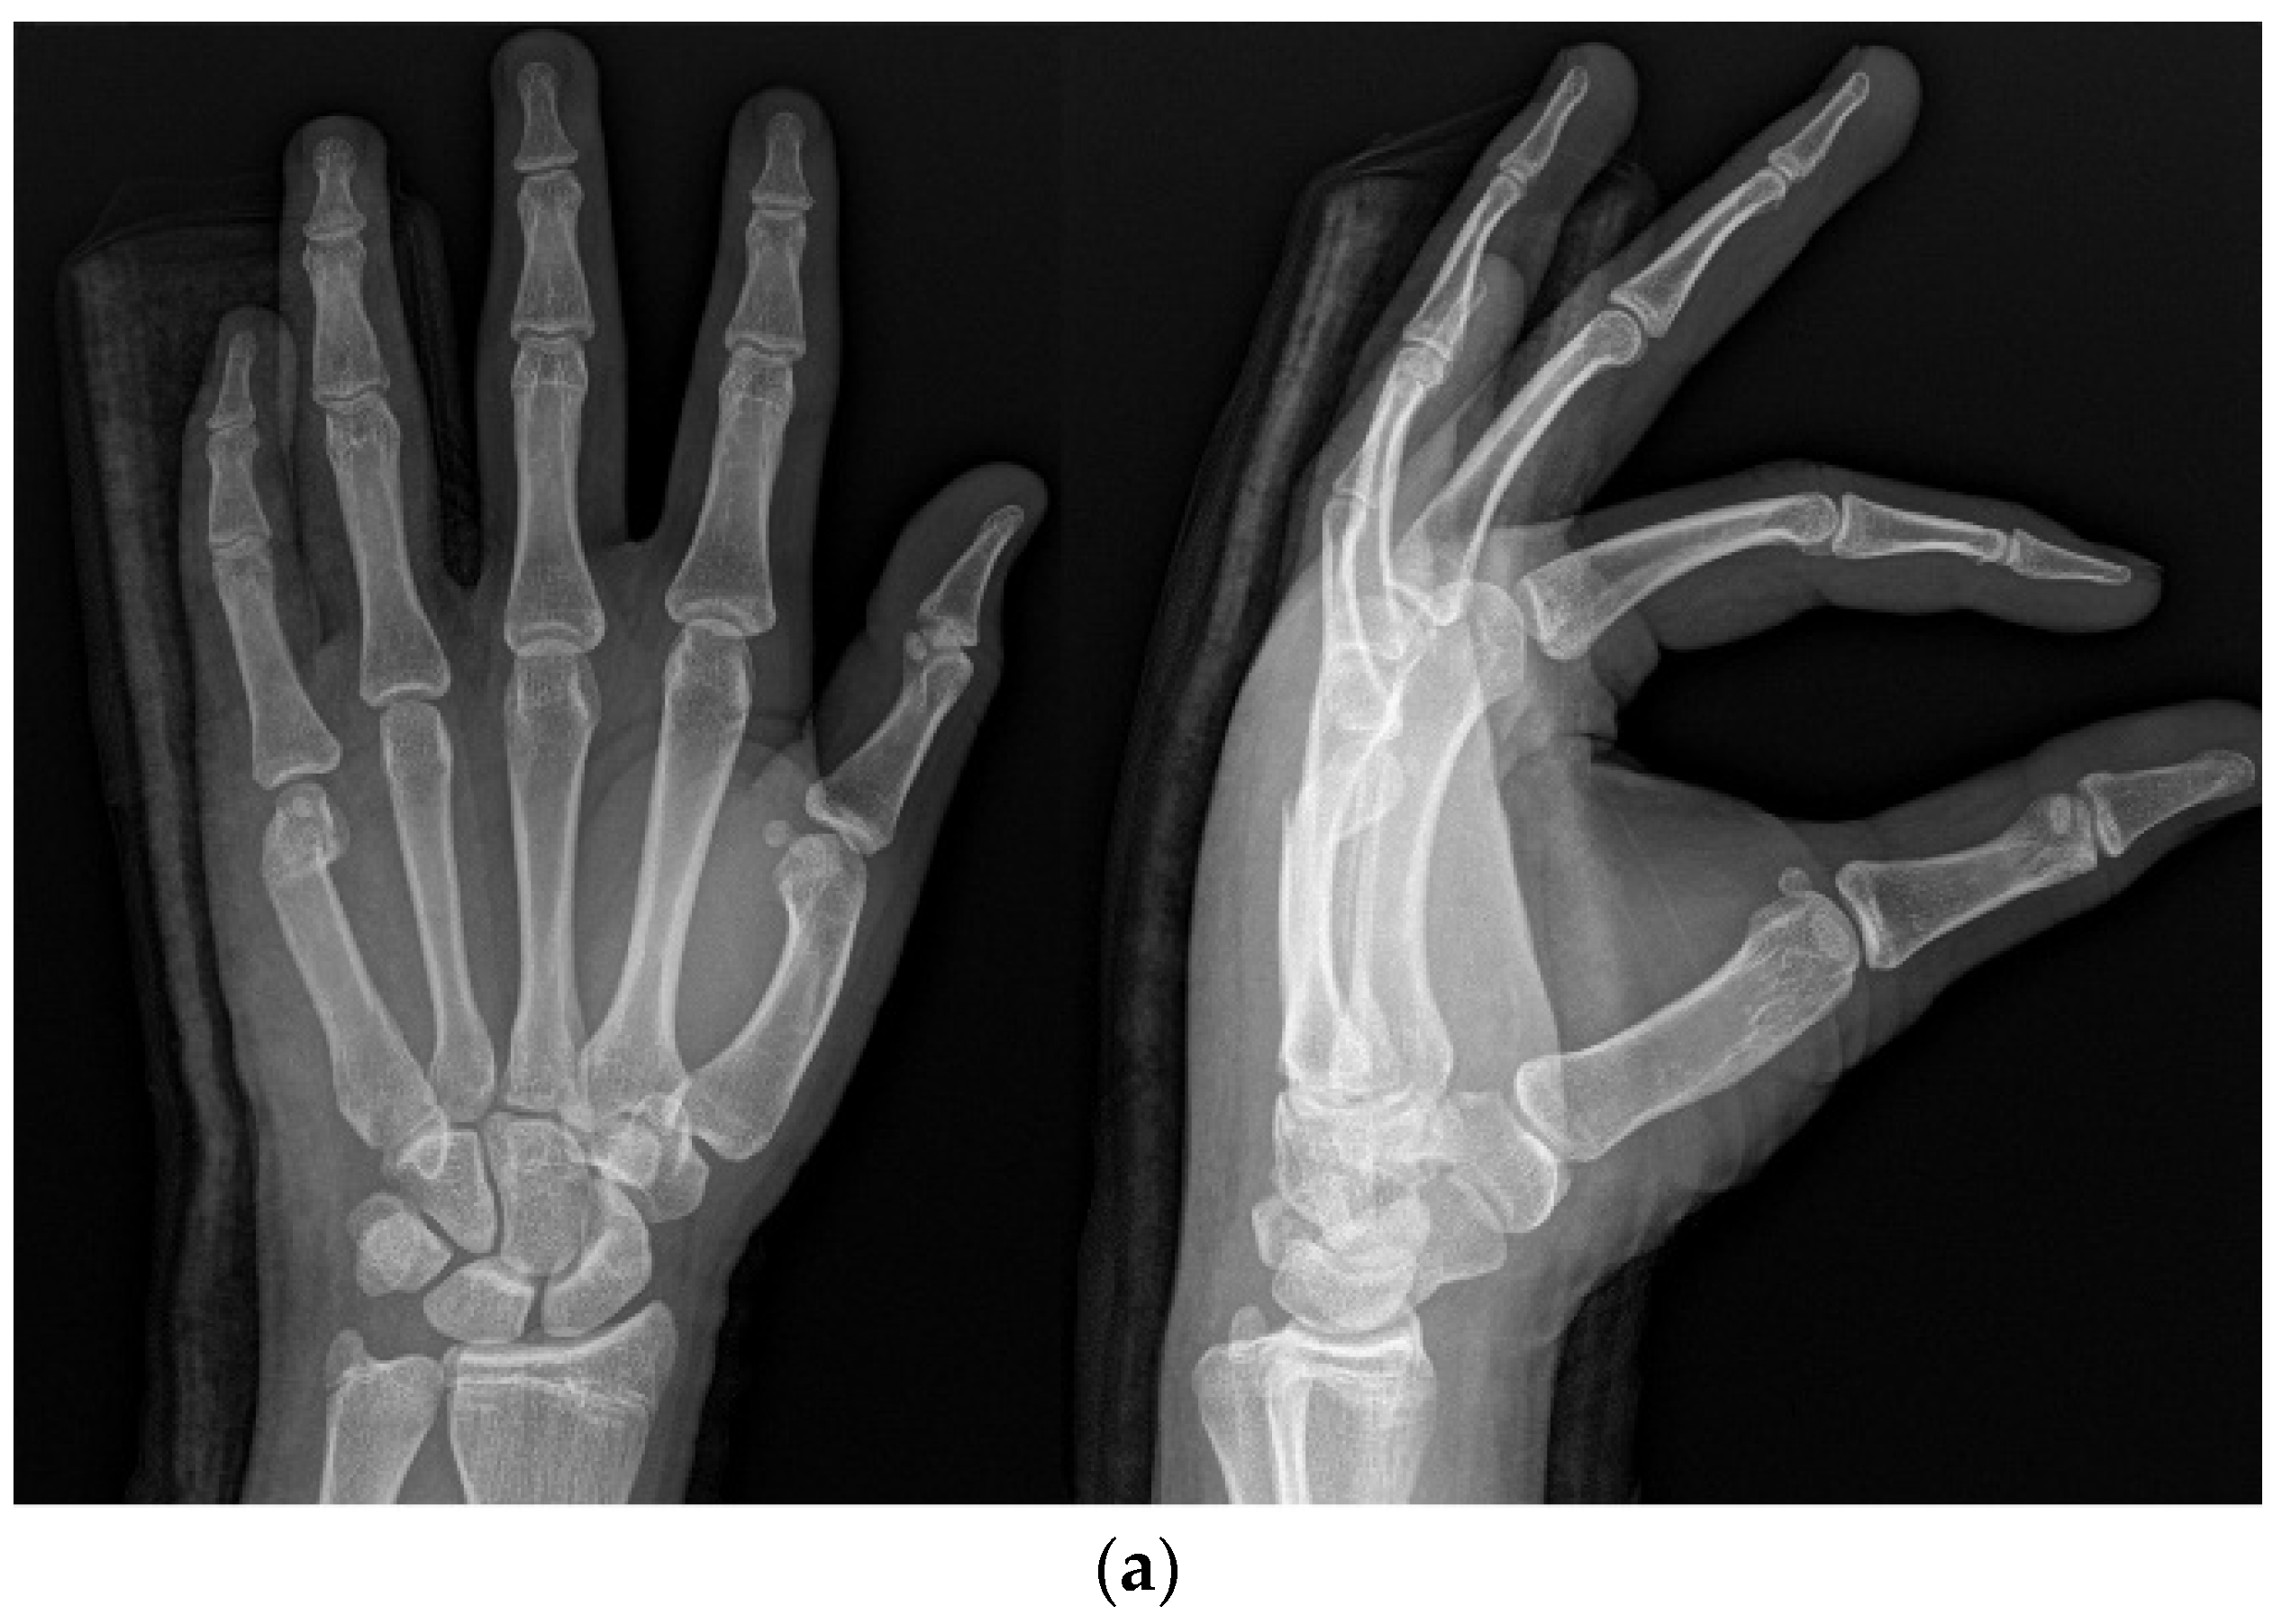

2.2. Methods

2.3. Surgical Technique